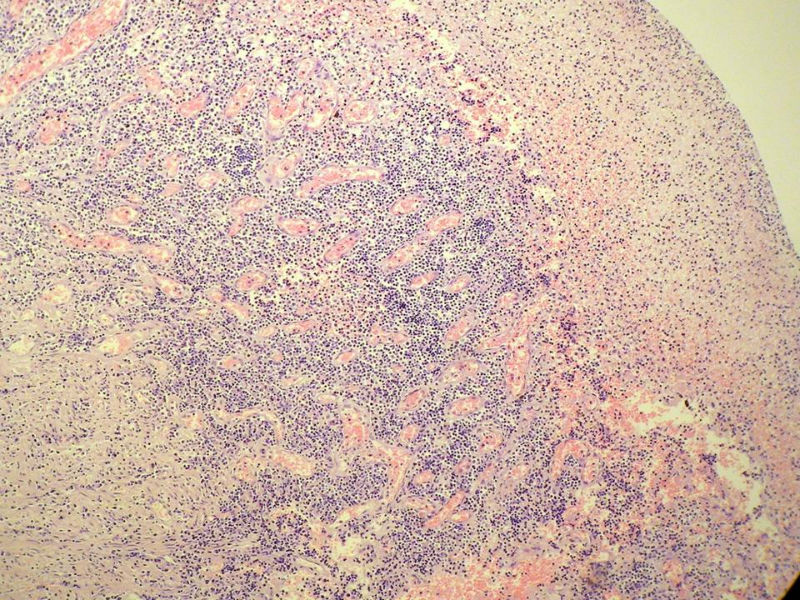

女,53岁,横结肠有9X6厘米大小溃疡,手术切除。

中老年人,溃疡很大,可见淋巴浆细胞样细胞弥漫浸润,散在大细胞,疑非霍奇颈淋巴瘤,倾向MALT伴浆样分化,不知是否破坏肌层?可否传肌层图?需IHC标记,鉴别淋巴瘤、腺癌及其它。

肉眼观仅是溃疡?有没有肠壁增厚、隆起?周围粘膜情况?肌层情况?有淋巴浆细胞样细胞、中心细胞,散在少量不成片的大细胞,不排除MALToma伴大细胞转化。

本例肉眼溃疡如溃疡性结肠炎,肠壁无明显增厚,表面辅以坏死,溃疡边缘稍隆起。镜下淋巴样细胞局限在粘膜层,肌层未见。谢谢!